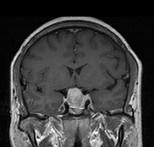

问题 男,41岁,头昏伴头痛1年,请根据所提供图像,选择最可能的诊断()

选项 A.(鞍区)脑膜瘤 B.(鞍区)颅咽管瘤 C.(鞍区)生殖细胞瘤 D.(鞍区)转移瘤 E.(鞍区)垂体腺瘤

答案 E